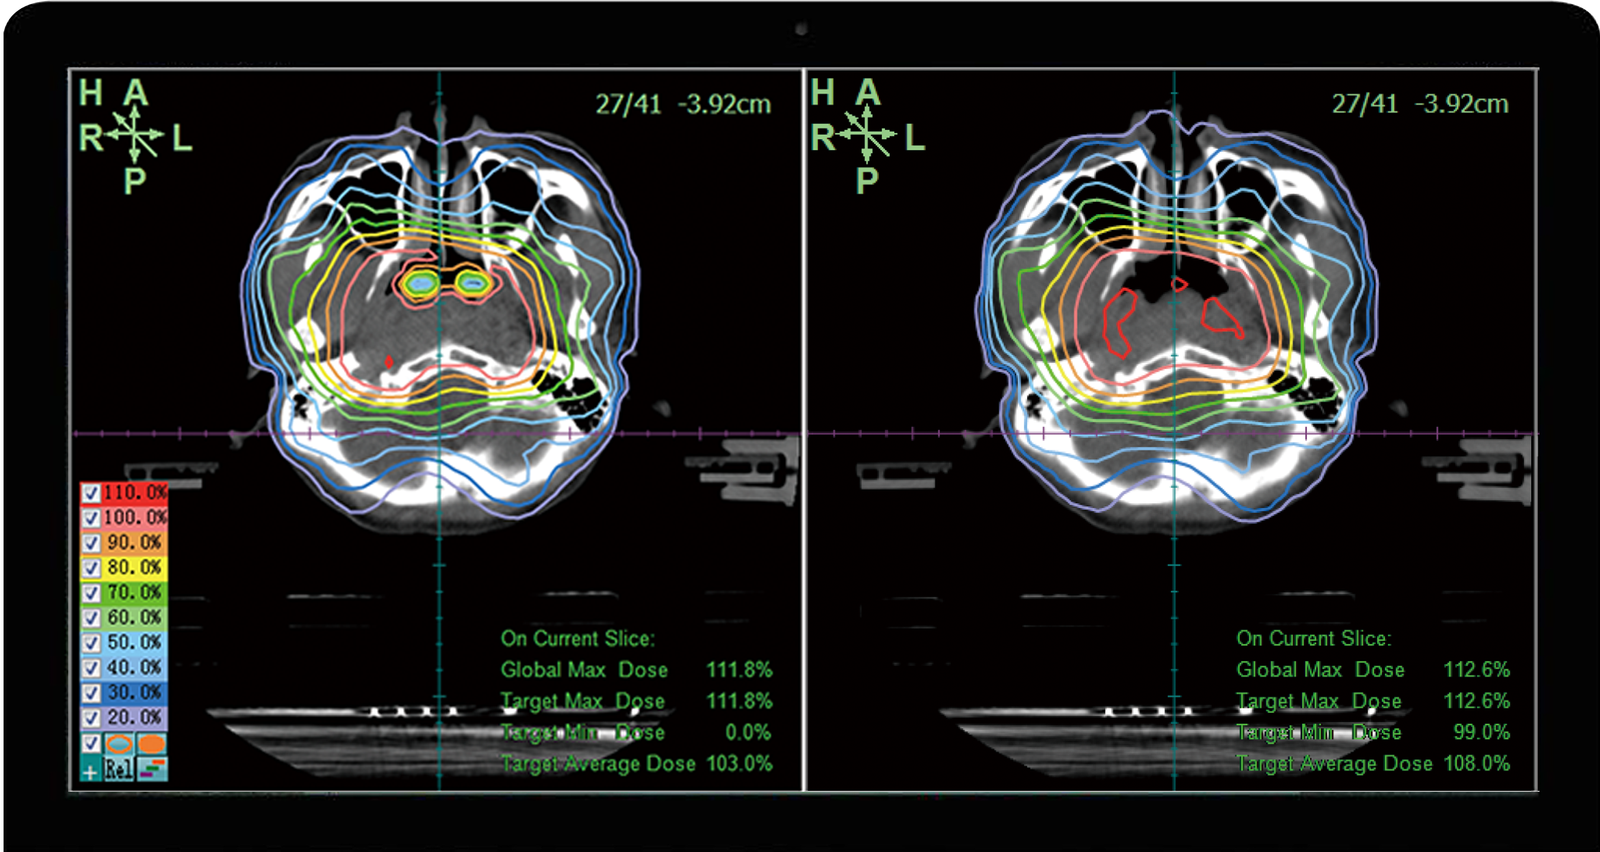

Orthogonal double layer multi-leaf collimator

VenusX is mainly composed of a radiation head, kV and MV imaging systems, treatment beds and other auxiliary systems. It contains three-dimensional conformal radiotherapy, intensity modulated radiotherapy, rotational radiotherapy and other treatment modes and is equipped with kV-kV, kV-MV, MV- MV, CBCT and other hybrid image-guided positioning. Automatic QA facilitates machine quality control, thereby improving the accuracy of patient treatment. The orthogonal double-layer multi-leaf collimation technology used in this product is the first of its kind in China, which can effectively improve the dose conformity and dose uniformity of the target area, better protect the organs at risk, and meet the clinical demand for precise treatment of complex cases. , this innovation has significant clinical advantages and a large number of patients will benefit from it.

TiGRT-TPS

The Monte Carlo planning system based on GPU acceleration can quickly and accurately complete 3D CRT / IMRT / VMAT / SRS.SBRT plan production.